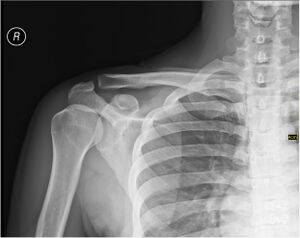

«Плечо» в анатомическом понимании.

Плечо́ (лат. brachium) — отдел верхней конечности. Оно располагается между плечевым поясом и предплечьем, и соединяется с ними посредством плечевого сустава и локтевого соответственно.

Скелет[править | править код]

Каркасом плеча служит плечевая кость.

При травмах плеча возможно повреждение нервов и сосудов, а также переломы плечевой кости, наиболее частой локализацией которых является шейка плечевой кости[1].